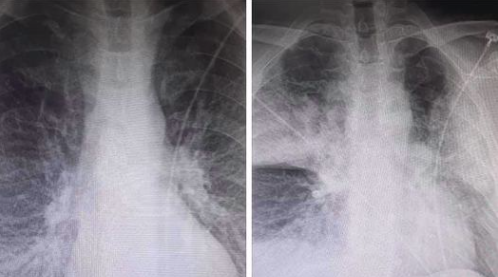

Οι δύο ακτινογραφίες, που ανήρτησε στο Facebook ακτινολόγος από το ΚΑΤ, προκαλούν σοκ, καθώς σε αυτές αποτυπώνεται η ραγδαία επιδείνωση που προκαλεί ο κορωνοϊός στους ασθενείς.

Ειδικότερα, ο κ. Μάνος Καρράς σημειώνει ότι οι δύο ακτινογραφίες ενός 38χρονου, ο οποίος είναι καπνιστης και διαβητικός, έχουν καταγραφεί με 7,5 ώρες διαφορά.

Η πρώτη είναι από την εισαγωγή ασθενή στις 12 το μεσημέρι με 98% κορεσμό οξυγόνου και η δεύτερη, η επαναληπτική, πραγματοποιήθηκε στις 19:30 με τον ασθενή να είναι πλέον με μάσκα οξυγόνου.

Σύμφωνα με τον κ. Καρρά τα «σύννεφα» στη δεύτερη ακτινογραφιά συνήθως σημαίνουν υγρό οίδημα φλεγμονή και «είναι κομμάτι του πνεύμονα που “δεν αναπνέει”».